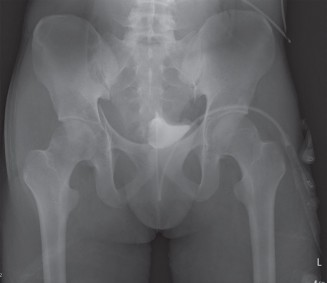

Clinical and Radiographic Imaging

- Initial AP Pelvis and Cross-Table Lateral Hip Radiographs: These are crucial for confirming the diagnosis, classifying the dislocation type, and identifying gross associated fractures.